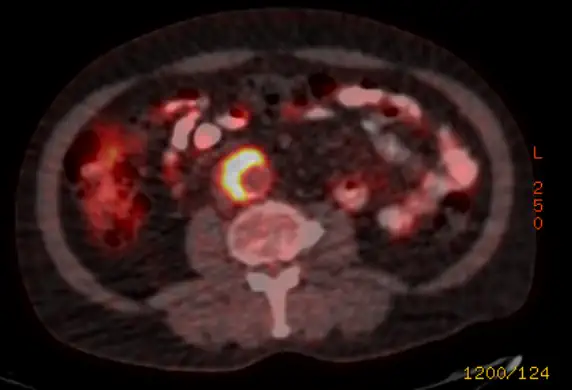

An iliac artery aneurysm is a dilatation of the iliac artery. A normal iliac artery measures up to 1 cm in diameter. An iliac artery that is wider than that is aneurysmal.

Isolated iliac artery aneurysms are uncommon. For reference, aortic aneurysms are perhaps present in 4% of people. An aneurysm in the iliac artery exists in 0.1%. These aneurysms are more common in conjunction with an aortic aneurysm. In any case, symptoms are rare. That is why diagnosis is usually incidental. Abdominal or even lumbar imaging may show this finding. The aneurysms are categorized by location: internal, external or common iliac artery. Common and external iliac artery aneurysms are actually more common than in the internal iliac artery.

An aneurysm in the iliac artery may stay asymptomatic. However there may be complications. These include rupture, thrombosis and distal embolization.

Rupture can result in death in as many as 80%. Because of this once these aneurysms are found, many would advocate preventative treatment. There is a claim that observation can lead to missing an aneurysm that may grow and rupture.